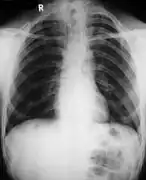

Diagnosis

Different features of the dysostosis are significant. Radiological imaging helps confirm the diagnosis. During gestation (pregnancy), clavicular size can be calculated using available nomograms. Wormian bones can sometimes be observed in the skull.[20]

Diagnosis of CCD spectrum disorder is established in an individual with typical clinical and radiographic findings and/or by the identification of a heterozygous pathogenic variant in RUNX2 (CBFA1).[21]